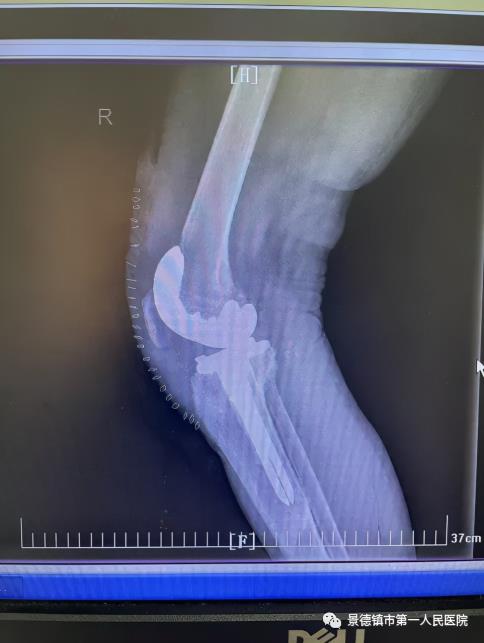

經(jīng)過屢次術(shù)前研討,袁志峰與手術(shù)隊伍醫(yī)生劉會文一同研討出手術(shù)計劃。行外表膝關(guān)節(jié)置換術(shù),盡快的保留患者更多的骨量,為20年乃至30年之后面對的再次置換供應(yīng)一個豐富的骨量貯備。并借用現(xiàn)在醫(yī)療行業(yè)最新的3D數(shù)字打印技巧,精確進行截骨和假體安頓,有效以免術(shù)后患者兩側(cè)因軟組織不平衡而導致的力線偏移,假體就愈加安穩(wěn),應(yīng)用的壽命愈加長。

8月23日,是程小華“重獲新生”的日子,1個半小時的手術(shù)流程,在程小華家人心里像過了一個時代如此長。當?shù)孟な中g(shù)十分順利后,他的家人心里好像放下一起大石。此段期間,骨二科的醫(yī)護職員時常在程小華的病房引導他復(fù)健,9月17日入院時,程小華已然能夠像常態(tài)人通常行走,他仍舊須要努力進行痊愈錘煉,逐漸修復(fù)大腿肌肉。